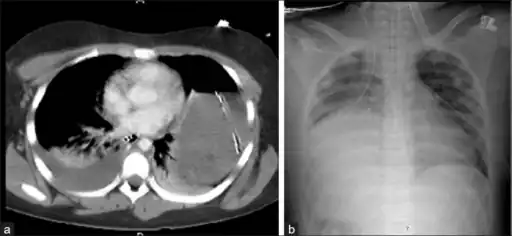

- Bilateral blunt diaphragmatic rupture a) confirmation of intrathoracic herniation indicates left hemidiaphragmatic rupture b) post operative image shows elevation of right hemidiaphragm adding suspicion of right diaphragmatic rupture

- Axial lower chest CT scan showing bowel herniation due to left diaphragmatic rupture